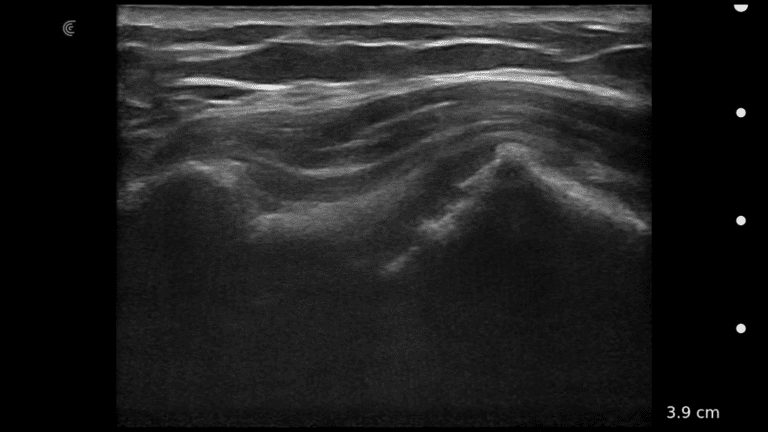

A survey scan of the elbow can identify some of the most common pathologies that cause acute and chronic elbow pain such as tendinosis of the common flexor or extensor tendons, joint effusion, or olecranon bursitis.